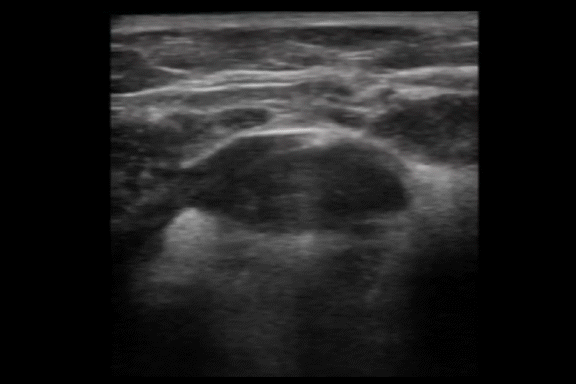

Precise Diagnosis with Ultrasound

Customized Salivary Gland Reduction

Ultrasound image of the submandibular area showing salivary gland before removal procedure.

Locate saliva gland and analyze size

MINE precisely analyzes the location and size of the salivary glands using the latest ultrasound examination.

Based on this, only the necessary portion of the enlarged glands is selectively removed,

reducing their size and creating a smoother jawline.